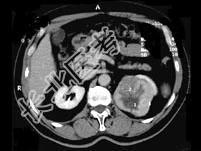

- 多项选择题男,65岁, 左侧腰背部胀痛伴无痛性全程血尿3个月余,CT平扫及增强检查如图所示, 下列说法正确的是 ( )

A、平扫时见左肾上极有一软组织肿块影,其边界较清楚

B、增强扫描肾皮质期可见肿块明显强化,其内亦有无强化区

C、增强扫描肾实质期可见肿块强化迅速下降,但密度比平扫时仍要高

D、考虑为左侧肾癌

E、考虑为左侧肾错构瘤